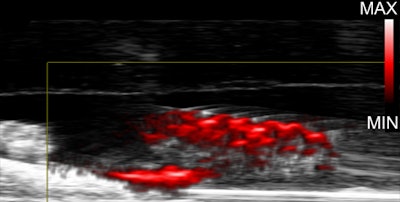

In the study, gold nanoparticles delivered to infected teeth and skin wounds are heated with near infrared lasers to destroy biofilms. Images and captions courtesy of Hajfathalian et al. Licensed under CC BY 4.0.

During a photoacoustic imaging test on the teeth, the nanoparticles produced clear signals, enabling the researchers to pinpoint where the biofilms had absorbed the dextran-coated particles on the teeth. As a comparison, they treated other infected teeth samples with the topical antiseptic chlorhexidine, according to the release.

Researchers were able to visualize biofilms in teeth treated with dextran-coated gold nanoparticles using photoacoustic imaging.